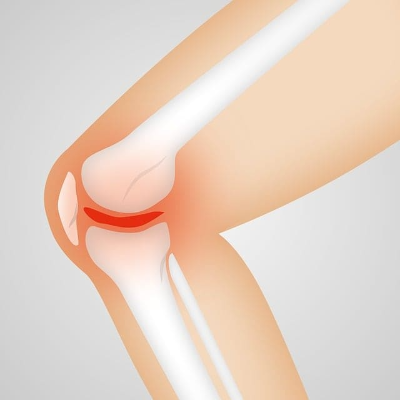

퇴행성 관절염, 연골 손상 등으로 무릎 인공관절 수술을 고민 중이라면 가장 먼저 궁금한 것이 ‘실제 부담금’입니다.

2025년 현재, 무릎 인공관절 수술의 전체 비용은 병원과 수술 범위에 따라 약 250만 원~350만 원 수준입니다.

그러나 건강보험 급여 항목으로 지정되어 있어 본인 부담금은 대략 20% 정도만 부담하면 됩니다.